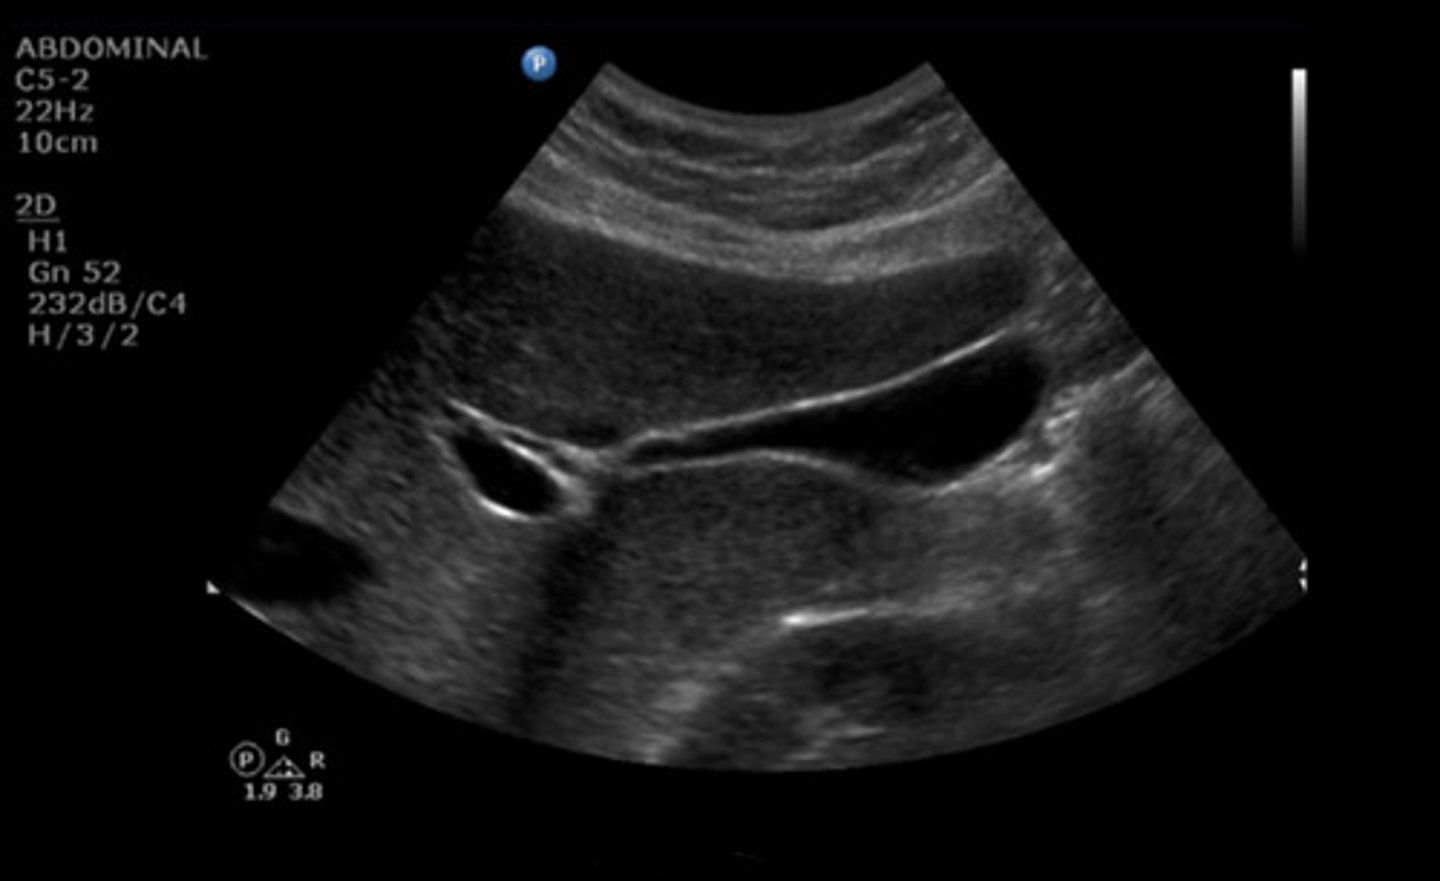

SAG GB RT LAT SUPINE

Identify the following;